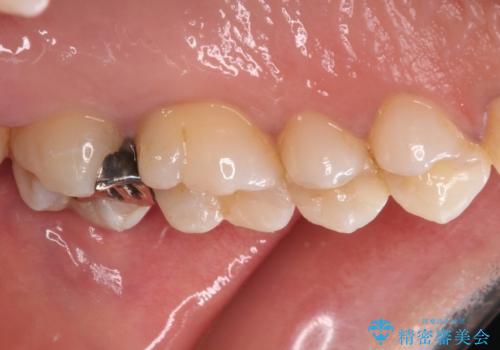

ゴールドインレーは銀歯のインレーやセラミックインレーと比べ、「技工操作の精度が高く、適合が著しく良い」というメリットがあります。特に上の奥歯は歯科医師の操作が行いにくいため、「適合の良さ」は再治療のリスクを防ぐ上でとても重要な要素となります。

上の奥歯は金属色が見えることもないため、審美的な問題は全くありません。

咬み心地はとても良好で、全く違和感がなく、患者様には大変満足していただきました。